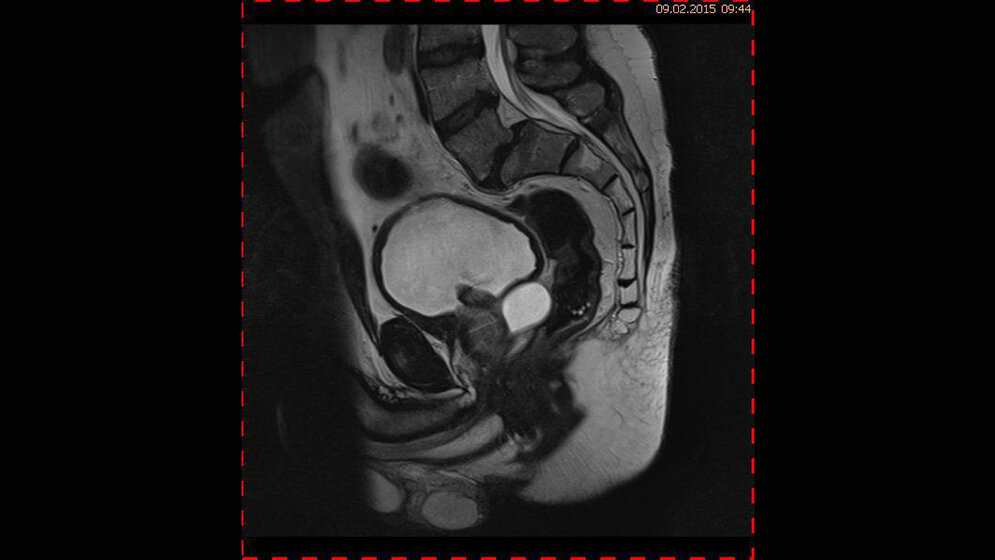

Das Fallbeispiel 1 demonstriert den Befund einer Samenblasenzyste bei einem 50-jährigen Mann, der über tiefsitzende Rückenschmerzen, progredient bei Belastung klagte und über eine Dysurie. Die Miktion war zunehmend erschwert. Die Kernspintomographie konnte eine Degeneration der lumbalen Bandscheiben mit multisegmentalem Bulging nachweisen und eine Spondylolisthese °1 nach Meyerding bei einer Spondylolisthesis vera im Segment L5/S1. Zusätzlich war bei großem FOV auch eine Hypertrophie des Prostatamittellappens erkennbar sowie eine unkomplizierte Zyste der Samenblasen mit ca. 3 cm (Abb. 1.1 bis 1.4).

Abb. 1.2: koronales MRT (T1 TSE, 1,5T): liquorintenses (hypointenses) Signal der Zyste

Abb. 1.3: koronales MRT (T1 TSE mit FS nach KM, 1,5 T): Signalanstieg der Zystenwand der sonst unkomplizierten Zyste

Abb. 1.4: transversales MRT (T1 TSE mit FS nach KM, 1,5 T): liquoräquivalentes Signal der Samenblasenzyste